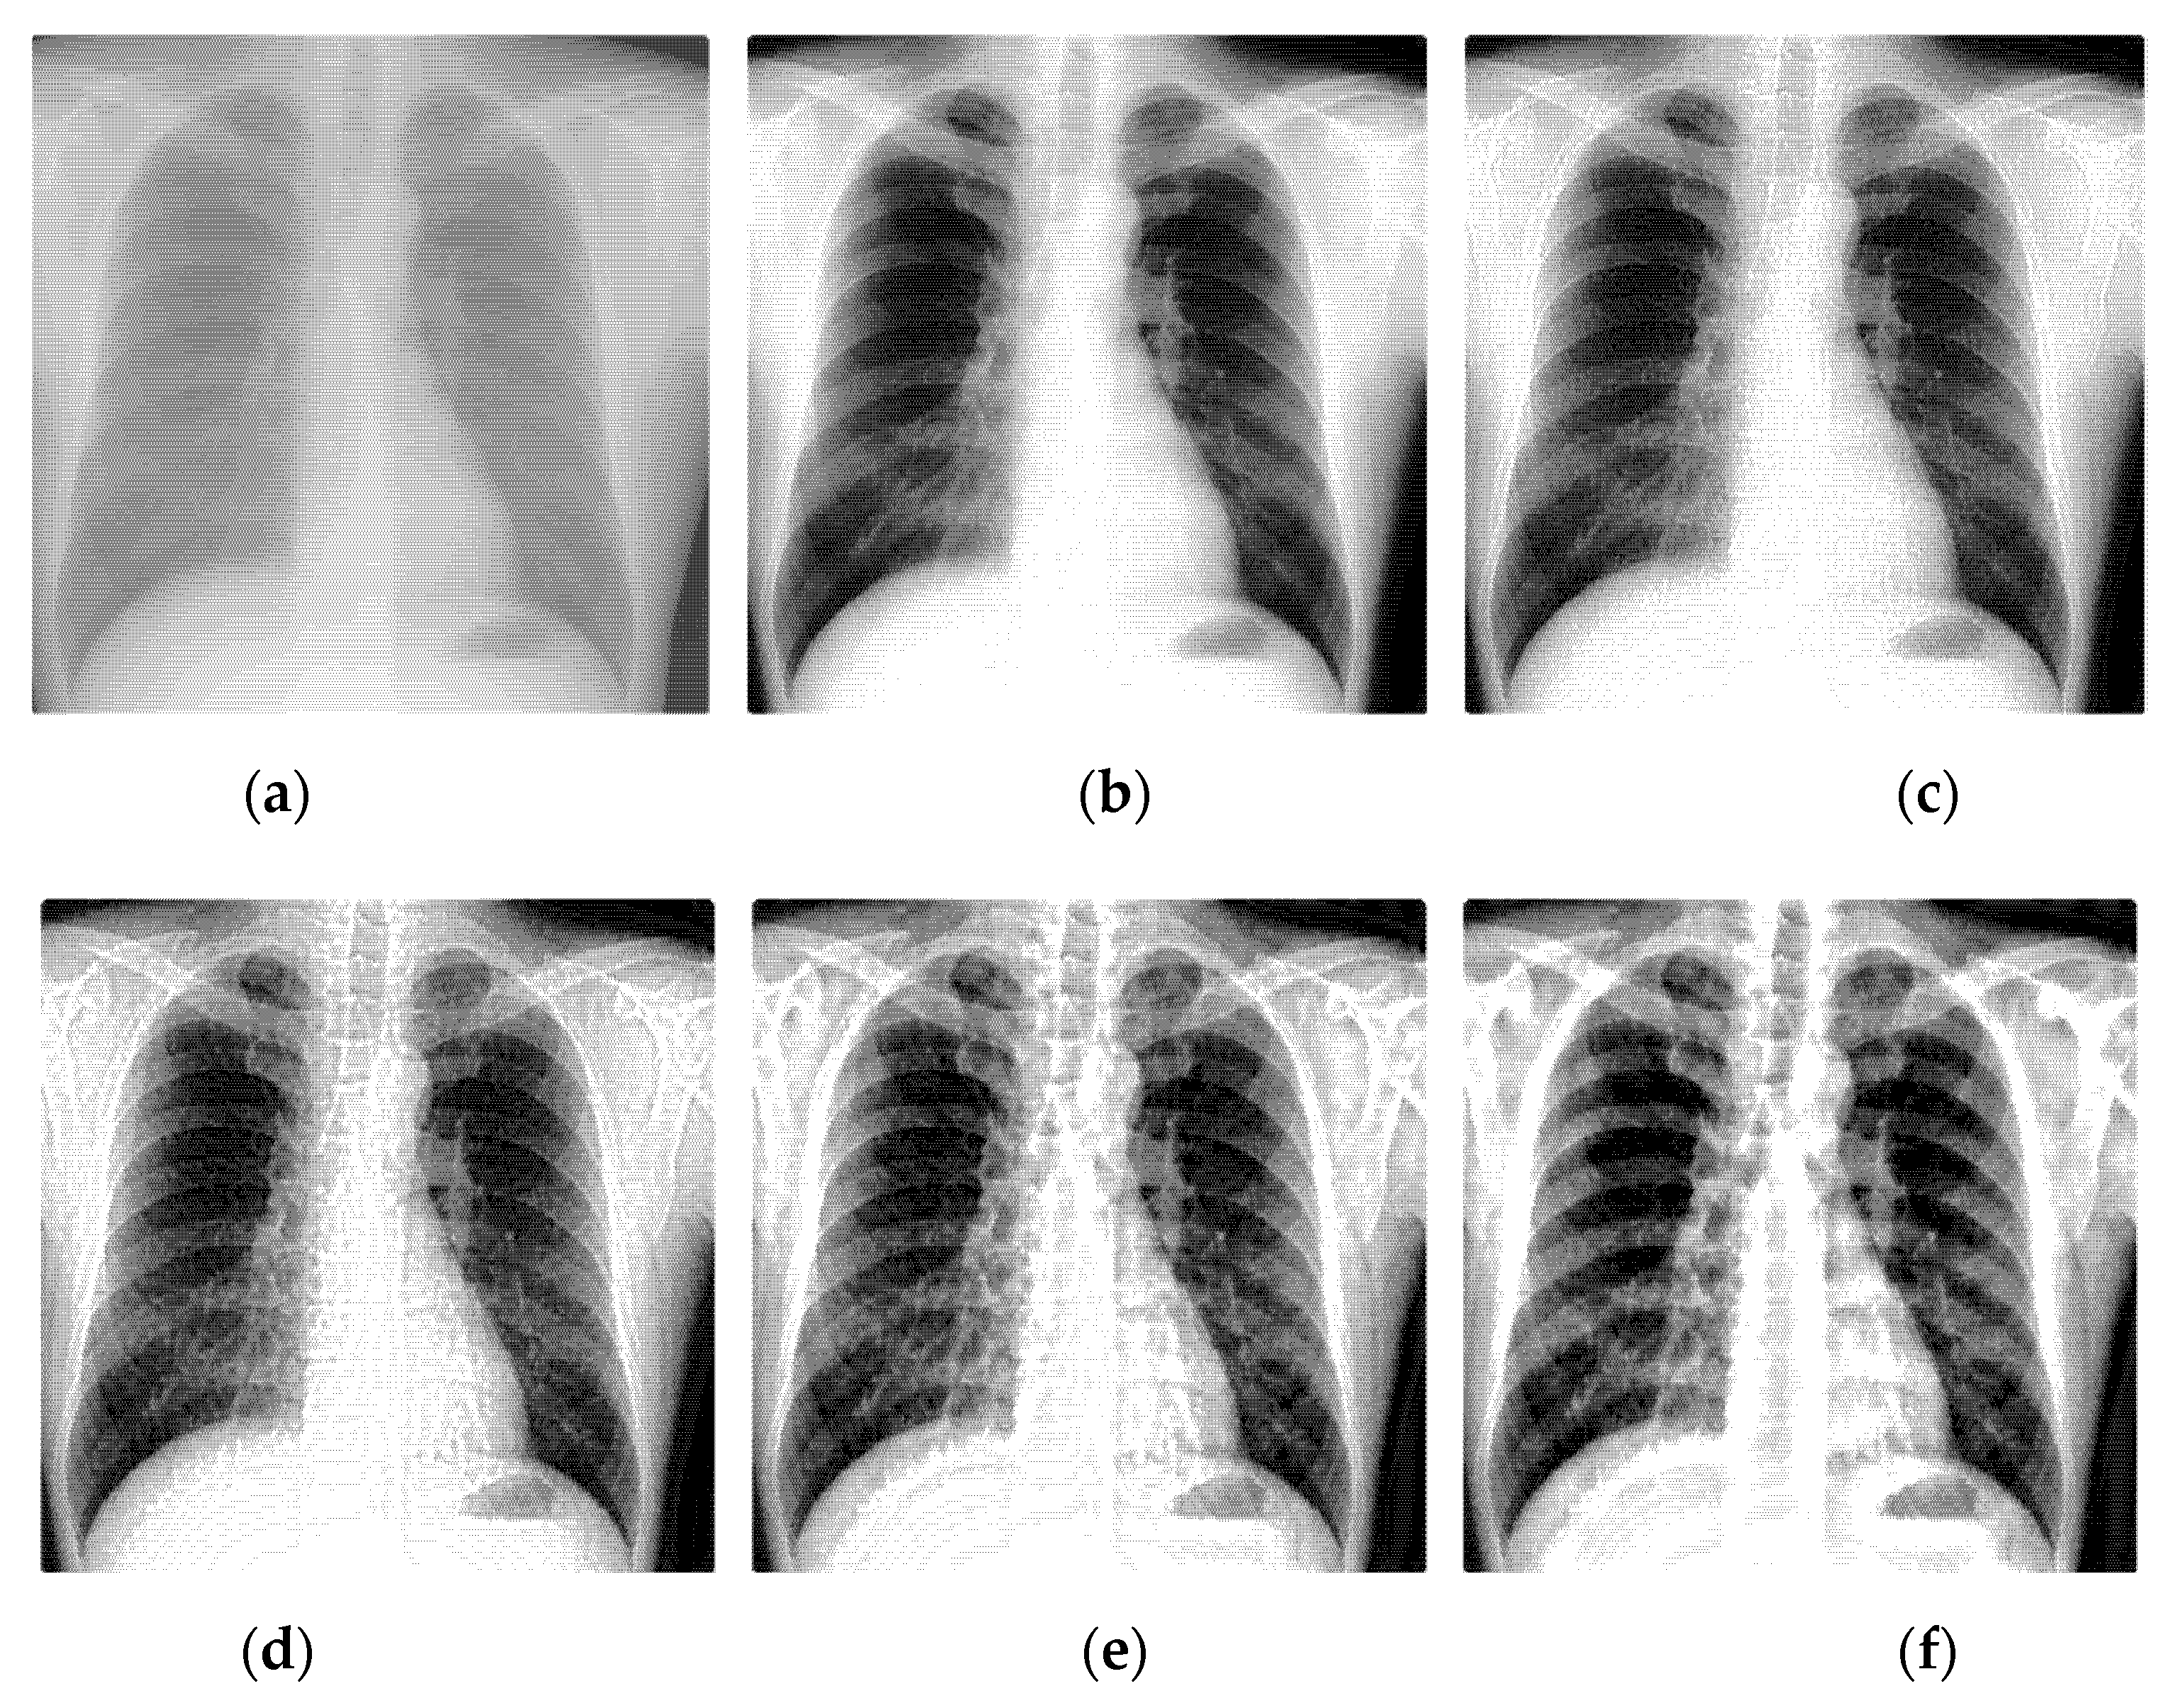

Select two representative medical images for analysis: Image 1 with the size of 440 × 440 and image 2 with the size of 1024 × 1024 . The enhanced X-ray images obtained under different decomposition levels are shown in Figure 3 and Figure 4 where (a) is the original image, and (b–f) corresponds to the decomposition levels j equal to 1–5. When the number of scale decomposition levels is j , NSST decomposition requires 2 j times of image and filter convolution; the running time of the algorithm gradually increases. Observing the image, the image contrast has been significantly improved after histogram equalization. When the decomposition scale j 3 , with the increase of the NSST decomposition scale, the boundary and texture features of the image are gradually obvious, and the detailed information is enhanced. When 5 j > 3 , the enhancement effect is further improved; the change is not significant.

Figure 4. The enhanced effects of different decomposition levels on the X-ray image 2. (a) is the original image, and (bf) corresponds to the decomposition levels j equal to 1–5.